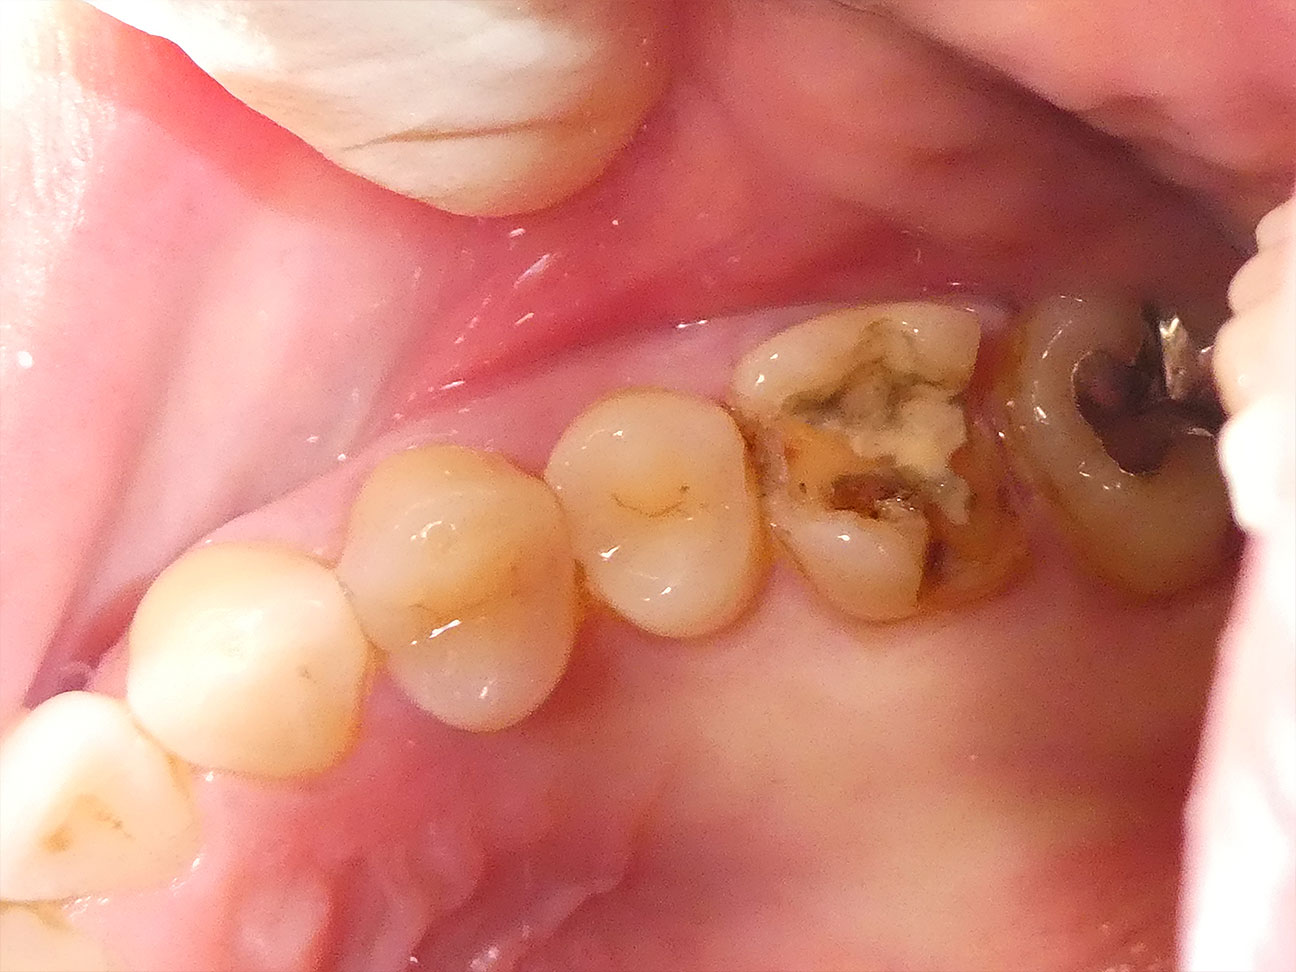

STEP3 金属の除去と虫歯の治療

保険で治療していた金属の詰めものを除去します。その後、齲蝕検知液を用いて丁寧に時間をかけ虫歯を取ります。ご覧のように銀歯を外すととても複雑な形をしているため、時間も手間もかかるのが虫歯治療で決して簡単な治療ではありません。この患者さんは歯の後ろ側(遠心口蓋側)が虫歯で大きく失われていたので、天然歯の強度を保ちつつ労を惜しまず虫歯を取りきります。